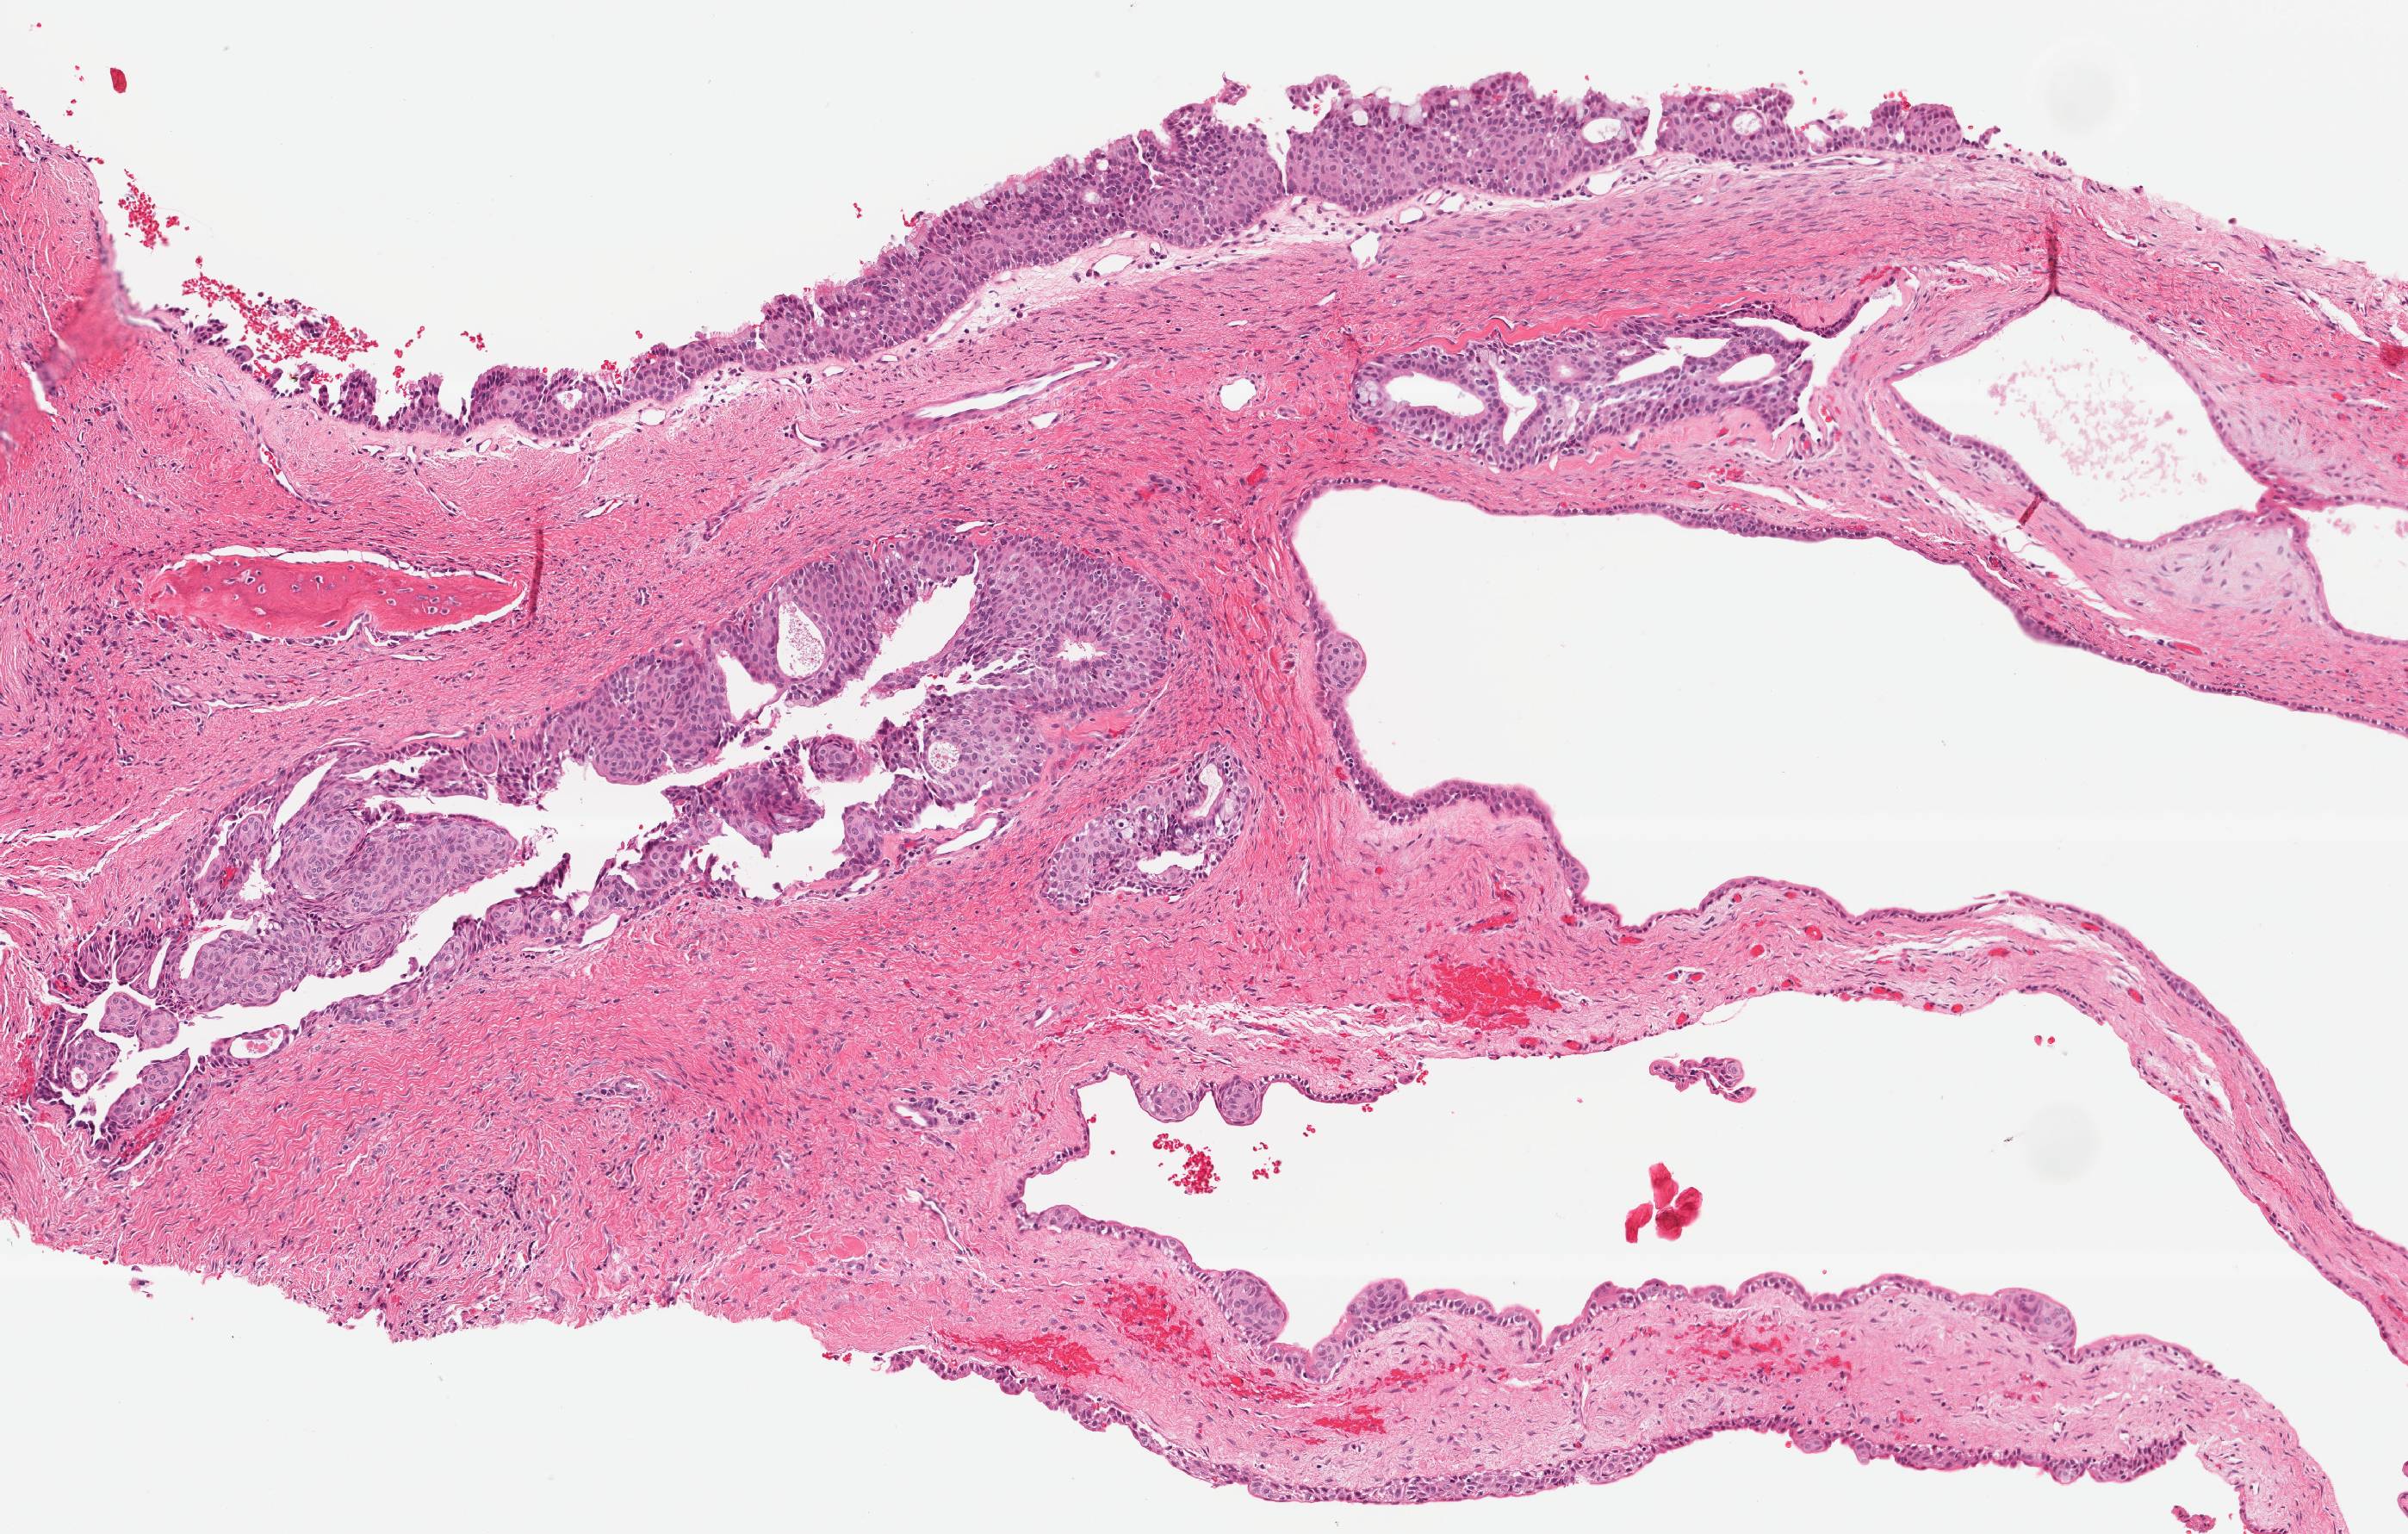

Microscopic (histologic) description

- Nonkeratinized or slightly basaloid epithelial cyst lining which may exhibit a number of microscopic parameters

- The combination of specific microscopic parameters is important in making an accurate diagnosis

- Presence of 7 or more microscopic parameters predictive of diagnosis; see Table 1 - Head Neck Pathol 2011;5:364

- Most helpful microscopic parameters: Table 2 - Head Neck Pathol 2011;5:364

- Intraepithelial microcysts, crypts or duct-like spaces:

- Most commonly lined by a single layer of cuboidal to columnar cells similar to surface cells, less commonly lined by mucous goblet cells

- Microcysts:

- May contain mucous pools, eosinophilic material, or appear empty

- May open onto surface of lining epithelium

- May give glandular or pseudoglandular structure appearance

- Epithelial spheres or plaque-like thickenings:

- Epithelium in these plaques exhibits swirling or spherule formation

- May protrude into cyst lumen or extend into underlying connective tissue wall

- Identical to structures present in lateral periodontal cysts or botryoid odontogenic cysts or soft tissue odontogenic cyst, gingival cyst of adult

- Multiple cyst compartments:

- Multiple cystic spaces similar to those seen in botryoid odontogenic cysts

- Variable thickness of the cyst lining

- Papillary projections or "tufting" of epithelium into cyst lumen:

- Papillary projections may be formed by several microcysts opening onto luminal surface of the cyst lining or be formed independent of microcysts

- Clear or vacuolated cells:

- Cells with clear cytoplasm which may be present in basal or parabasal layers

- In areas of attenuated cyst lining, clear basal cells may be directly subjacent to the surface eosinophilic cuboidal cells

- Surface eosinophilic cuboidal cells (hobnail cells):

- Present on luminal surface of cyst lining; resemble cuboidal cells of the reduced enamel epithelium that lines dental follicles and dentigerous cysts

- May demonstrate cilia

- Not specific for GOC diagnosis

Microscopic (histologic) images

Contributed by Kelly Magliocca, D.D.S., M.P.H.